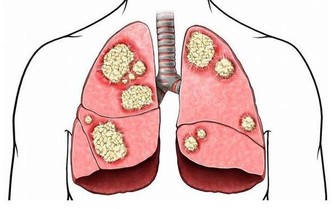

俗話說“傷在兒身,痛在娘心”,有時候孩子生病更令大人傷心,恨不得所有的痛苦由自己代替。今天要說的是白血病,聽到這個病相信很多人第一印象就是光著頭、戴著口罩的孩子,他們不能隨便外出,不能亂吃外面的餐飲,擔心交叉感染。看著孩子眼巴巴地望著窗外同齡小伙伴自由奔跑,大人心裡也不好受。

在兒童腫瘤數據中,超過一半的數據由白血病“貢獻”,而且還在以每年3-4萬的速度往上增加。在治療的同時我們也在深思,為什麼受傷的總是孩子?